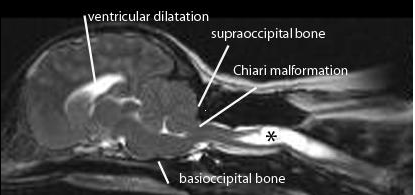

Chiari malformation

is an abnormality in the lower part of the brain called the cerebellum. Most cases of Chiari are congenital, meaning they are present from birth. In an individual with Chiari, the cerebral tonsils hang below the skull opening and into the spinal canal. The degree to which the tonsils extend can vary tremendously. The most common symptom of Chiari malformation is a headache, which begins at the back of the head (neck) and radiates upward. Other symptoms include visual problems; balance difficulties; vertigo and cranial nerve compression, resulting in apnea, swallowing difficulties, syncope or facial numbness. Chiari malformation can cause a fluid collection inside of the spinal cord, known as a syrinx. Some individuals may have hydrocephalus, a buildup of fluid in the ventricles of the brain.

Hydrocephalus occurs when excess cerebrospinal fluid builds up in the cavities (ventricles) within the brain. The fluid can increase the size of the ventricles, putting pressure on the brain, which can damage brain tissue and cause a range of impairments in brain function. Hydrocephalus can be diagnosed at any age, but occurs most frequently among infants and adults over 60. While surgical treatment for hydrocephalus can restore normal fluid levels in the brain, managing symptoms and functional impairments often requires additional treatments and therapies. Learn more about hydrocephalus.

Chiari Shown in Human & Dog MRI